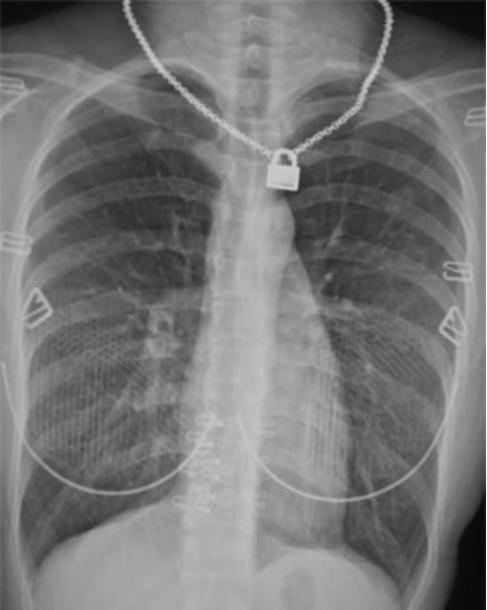

可见患者所戴的项链、吊坠、胸罩金属环、条纹状编织物和带扣影像。